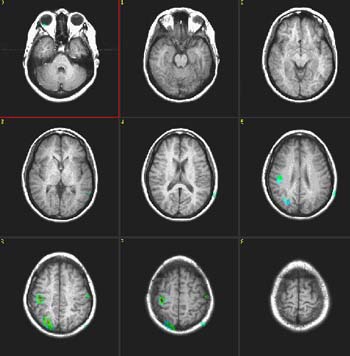

| Activación |

Corteza motora oral y facial, más grande en la derecha. Lóbulo parietal derecho. No se observa activación en el área de Broca. |